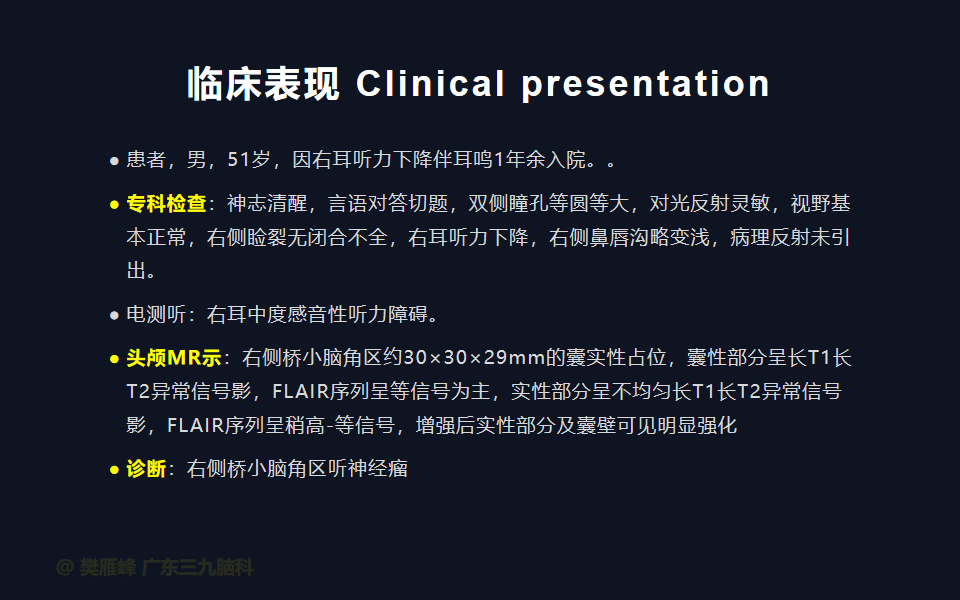

在这个二维手术视频中,展示了一种经枕下乙状窦后入路束膜下分离保留面神经的方法。患者是一名51岁的男性,有1年右耳听力下降伴耳鸣、无步态不平衡病史,术前有右侧轻度面瘫,神经影像学显示右侧桥小脑角区约30×30×29mm的囊实性占位,增强后实性部分及囊壁可见明显强化。他接受了经乙状窦后入路保留面神经的方法,术中肿瘤全切除,面神经被肿瘤挤压成薄膜状覆盖于三叉神经表面。术后面瘫加重,听力未能保留,神经影像学显示肿瘤全部切除。我们展示了安全的颅神经保护和肿瘤切除的细微差别和技术要点,以及手术技术。

在这段手术视频中,展示了一名51岁男性的病例,他因右耳听力下降伴耳鸣1年余发现的右侧听神经瘤。